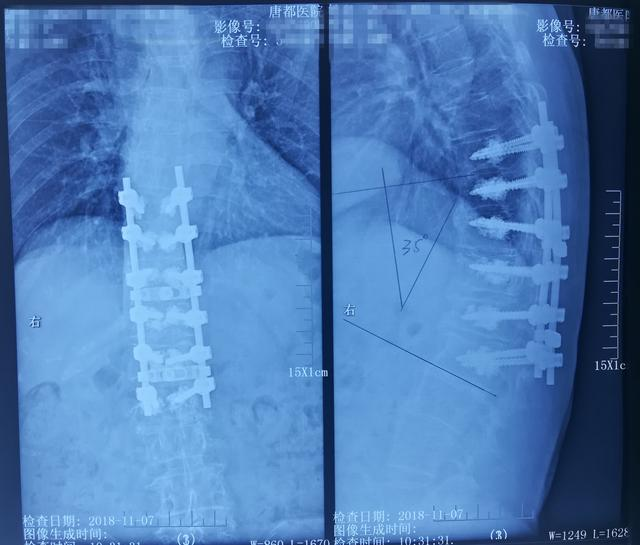

省骨科医院脊柱外三科标准经椎间隙四级截骨术治疗复发型脊柱后凸畸形

病例分享:胸腰段脊柱后凸畸形 - 好大夫在线